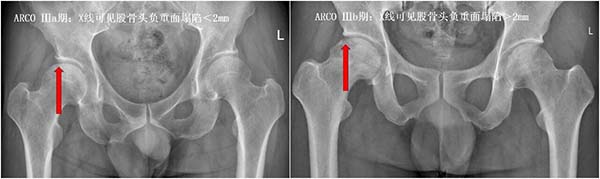

ARCO Ⅲ期:股骨头已经出现塌陷,关节功能开始受损,保髋难度明显增加,预后也会变差,部分人可能需要接受更复杂的保髋手术;